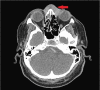

Figure 1

Axial CT scan of the orbits illustrating a solid mass along the nasal soft tissue extending bilaterally into the medial periorbital soft tissue. Bony nasal destruction is noted extending into the mid/superior nasal septum and anterior nasal cavity mucosa.